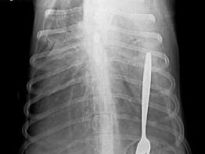

Şoke eden röntgen filmleri

Bu röntgen filmleri görenleri şaşkına çeviriyor!